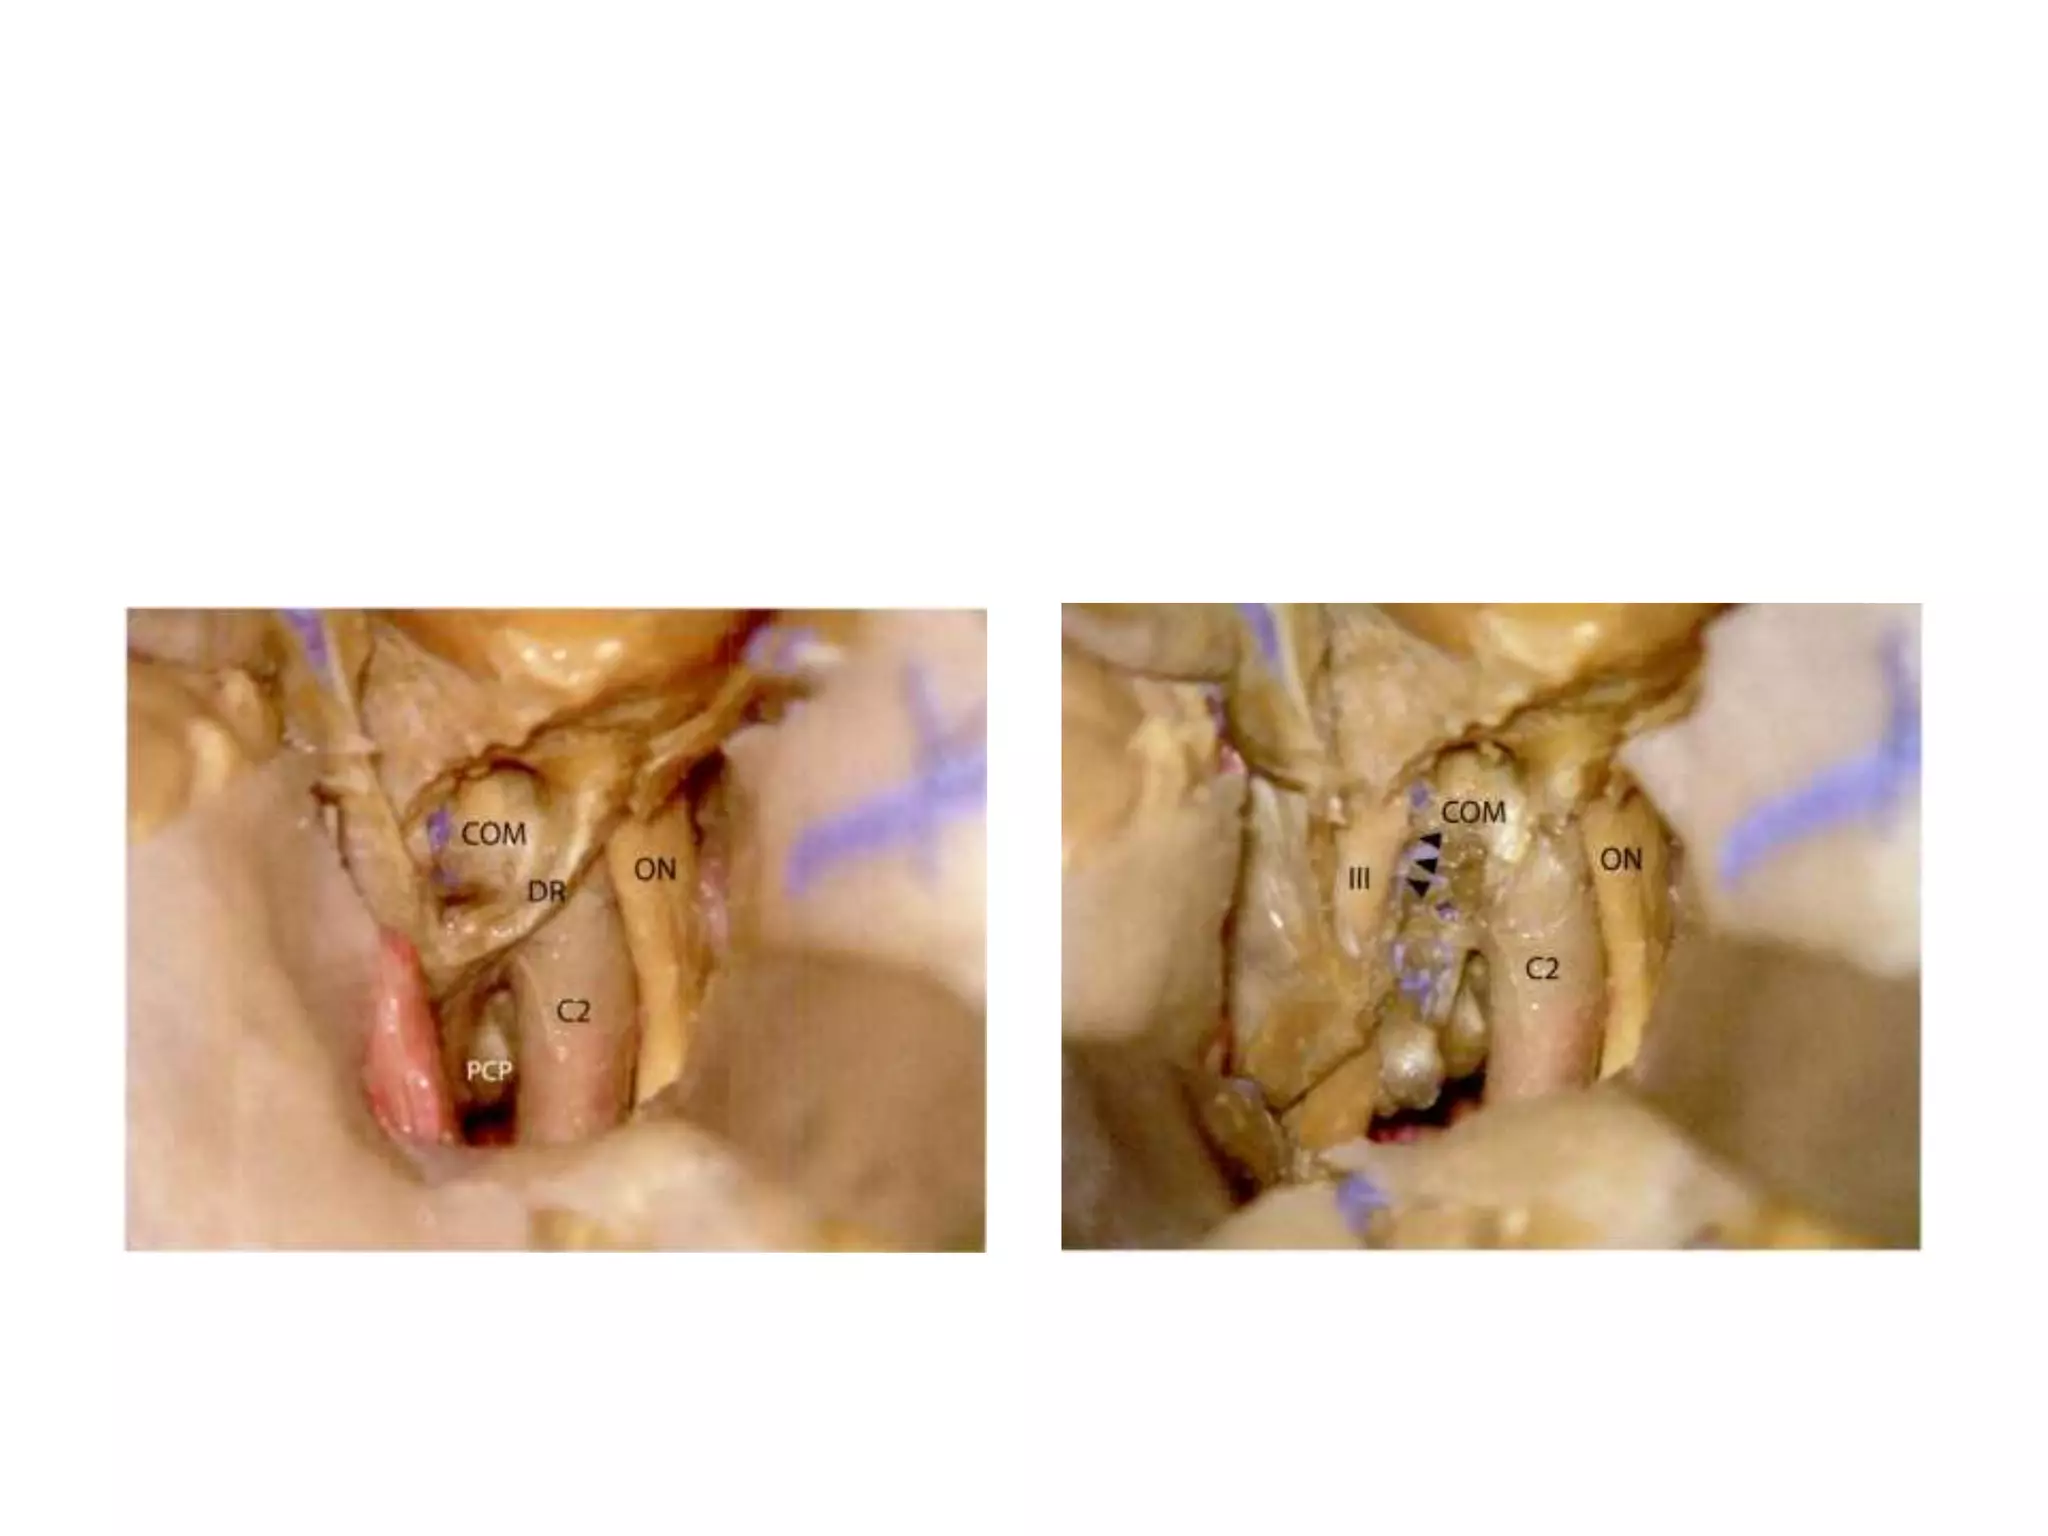

Fronto-temporal orbitozygomatic

transcavernous approach

COM= Caratico-occulomotor

membrane , DR = dural ring

Division of PComA

Fronto-temporal orbitozygomatic transcavernous approach COM=Caratico-occulomotor membrane , DR = dural ring